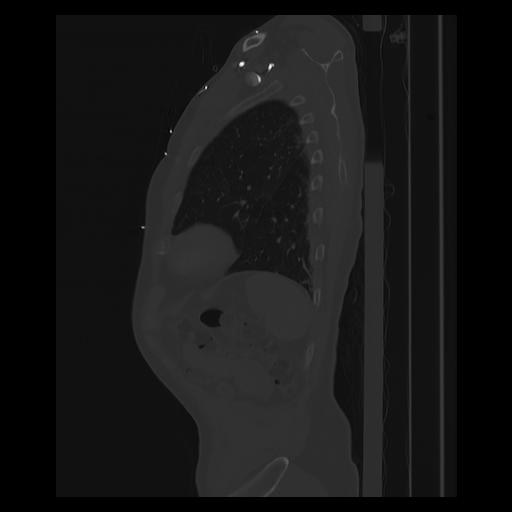

33 PULMON,CE,Sagittal,3.000,PULMON,Sagittal,